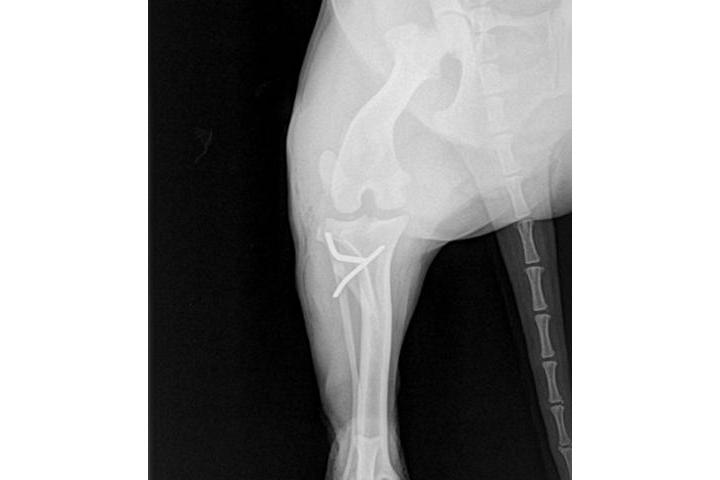

Rx control

por En la radiografía que acabo de publicar, que le hicieron a Snoopy ayer por la tarde, se aprecia perfectamente la diferencia posicional de las dos patitas. Nuestra Snoopy se está recuperando muy bien y mucho mas deprisa de lo que esperábamos. La rx se la hicieron en su veterinario de Reus y ahora esperamos la valoración del cirujano de Cambrils que la operó que la tiene en su poder las placas y el informe valorativo de los vetes de aquí. El decidirá si ya está preparada para la siguiente intervención o si por el contrario debemos darle un poco mas de tiempo. No debemos olvidar que aun no hace un mes que la operó y tenemos que ser cautos y asegurarnos de que su musculatura esté fuerte. Por otro lado, deciros que el coste de este control ha sido menor de lo que esperábamos, tan solo 30,-€ por la rx por lo que la hucha de Snoopy no se ha visto demasiado perjudicada. en un rato os pasaré la factura de ayer y el balance del mes en curso. un gran abrazo a tod@s.

rx de control